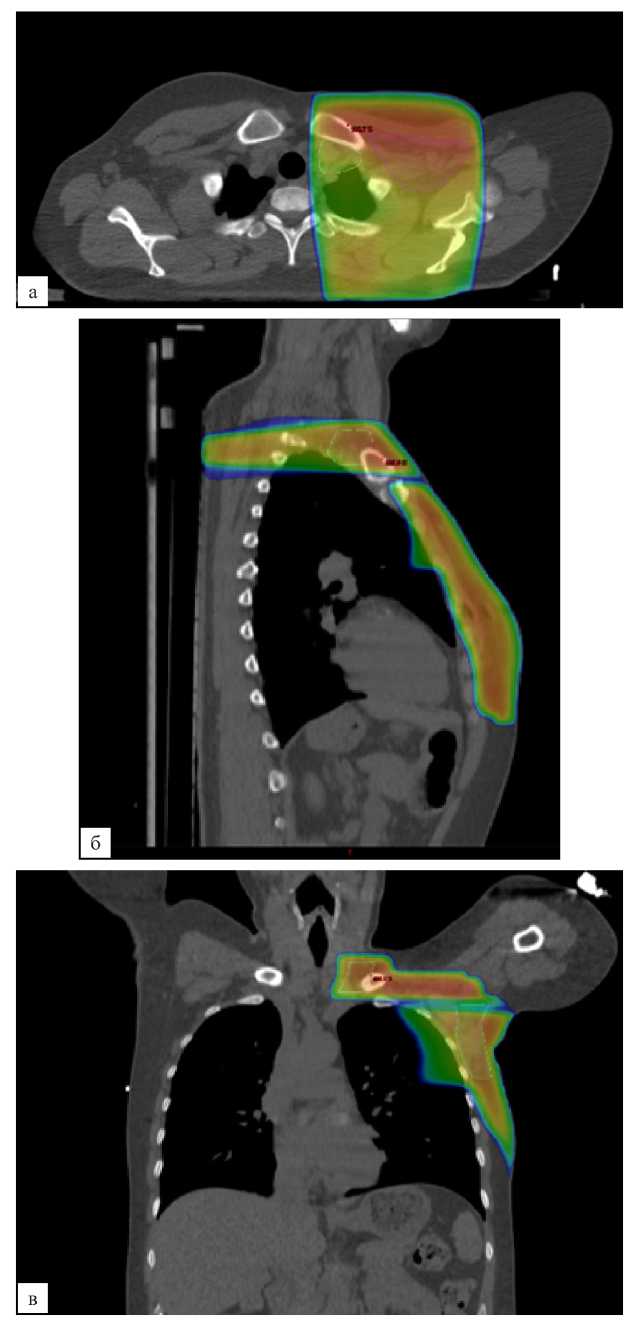

В контрольной группе послеоперационная лучевая терапия проводилась в стандартном объеме — облучение оставшихся тканей молочной железы (после органосохраняющего лечения) или мягких тканей передней грудной стенки (после мастэктомии) с подмышечными ЛУ I, II, III уровней и надключичными ЛУ (рис. 2, а, б, в). При планировании объемов облучения в исследуемой группе из объема облучения исключались подмышечные ЛУ III уровня и надключичные ЛУ (рис. 3, а, б, в). Оконтуривание всех указанных структур выполнялось согласно рекомендациям ESTRO от 2015 года [15].

Рис. 2 (а, б, в). Дозиметрический план лучевой терапии молочной железы, надключичных и подмышечных лимфатических узлов I, II, III уровней. а — аксиальная проекция; б — сагиттальная проекция; в — фронтальная проекция

Fig. 2 (а, б, в). Dosimetric plan of breast RT, supraclavicular and axillary lymph nodes of levels I, II, III. a — axial plane; б — sagittal plane; в — frontal plane